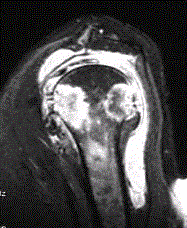

问题 患者女,71岁,双侧肩痛半年余。有较长SLE病史和激素用药史。行左肩X线平片、MR检查(下图)。 关于肩关节结核,下列描述正确的是

选项 A.肩关节结核病程进展快 B.肩关节为结核最好发部位 C.肩关节结核多为单纯性滑膜型结核 D.肩关节结核常常为双侧受累 E.侵犯滑膜、软骨和骨的结核为全关节结核

答案 E